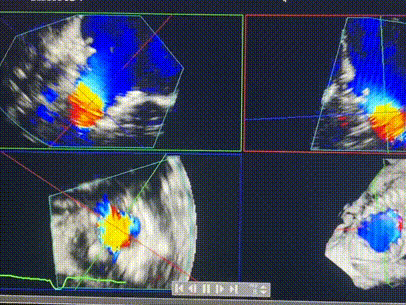

術(shù)前超聲提示重度三尖瓣反流

近日,西班牙阿爾瓦羅昆奎羅醫(yī)院 (Hospital Álvaro Cunqueiro)Rodrigo Estévez-Loureiro教授團(tuán)隊(duì)成功應(yīng)用LuX-Valve Plus經(jīng)血管三尖瓣置換系統(tǒng)為一例因三尖瓣大量反流導(dǎo)致的右心衰竭患者完成三尖瓣置換手術(shù),術(shù)后超聲顯示人工三尖瓣植入穩(wěn)定,瓣葉啟閉良好,僅殘余微量瓣周漏。患者在手術(shù)室即刻拔除氣管插管,血流動(dòng)力學(xué)改善顯著。此次手術(shù)也是LuX-Valve Plus于西班牙的首次臨床應(yīng)用,治療效果優(yōu)異。